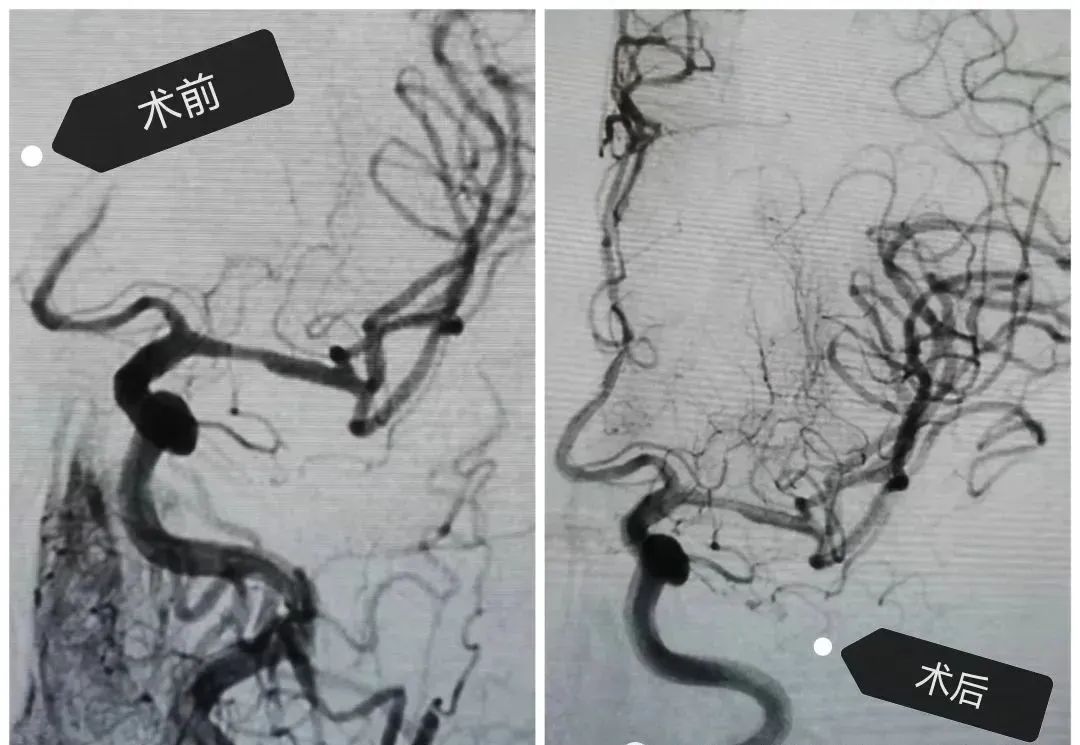

不幸的是溶栓2小時后,患者病情再次加重,出現(xiàn)不能說話,右側(cè)肢體全癱的病癥,考慮到再次梗塞的情況發(fā)生。卒中小組-神經(jīng)外科王芃主任緊急會診后建議全腦血管造影術(shù)(DSA)及介入治療,術(shù)中顯示患者左側(cè)大腦前動脈閉塞,需立即采取動脈內(nèi)開通技術(shù),再通大腦前動脈后幫助患者轉(zhuǎn)危為安。術(shù)后患者病情很快好轉(zhuǎn),語言和肢體功恢復(fù),經(jīng)短期康復(fù)后出院。

腦血管造影(DSA)

《中國腦卒中防治指導規(guī)范2021版》指出,我國腦卒中發(fā)病率逐漸年上升,且呈年輕化趨勢,目前是我國第一位死亡原因和致殘率最高的疾病。由于腦組織的特性,腦卒中一旦發(fā)病,很快且不可逆,因此時間就是生命,時間就是大腦,超早期治療是降低死亡率,減少致殘率最佳方法,腦血管造影是目前腦卒中病因診斷的金標準,介入治療創(chuàng)傷小,操作便捷,療效可靠,預(yù)后好。